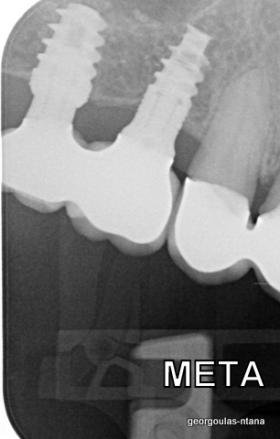

ΠΡΟΣΘΕΤΙΚΗ ΑΠΟΚΑΤΑΣΤΑΣΗ ΣΤΗΝ ΑΝΩ Κ ΚΑΤΩ ΓΝΑΘΟ ΚΑΙ ΤΟΠΟΘΕΤΗΣΗ ΕΜΦΥΤΕΥΜΑΤΩΝ ΜΕ ΚΛΕΙΣΤΗ ΑΝΥΨΩΣΗ ΙΓΜΟΡΕΙΟΥ

Ο ασθενής  προσήλθε στο ιατρείο μας θέλοντας να βελτιώσει την εμφάνιση των πρόσθιων δοντιών του και να αποκαταστήσει την υγεία κ την λειτουργία όλου του στόματος. Πραγματοποιήθηκε περιοδοντική θεραπεία κ ενδοδοντικές θεραπείες (απονευρώσεις) όπου κρίθηκε απαραίτητο και στη συνέχεια τοποθετήθηκαν 3 εμφυτεύματα, 2 δεξιά στις θέσεις του πρώτου κ δεύτερου γομφίου κ 1 αριστερά στη θέση του πρώτου προγομφίου. Κατά την  τοποθέτηση των 2 εμφυτευμάτων της δεξιάς πλευράς, πραγματοποιήθηκε κλειστή ανύψωση ιγμορείου με το σύστημα Piezotome-Intralift , τεχνική που εξασφαλίζει τη μικρότερη δυνατή επέμβαση κ τη μικρότερη μετεγχειρητική ταλαιπωρία (minimally invasive), καθώς κ αυξητικους παράγοντες PRF. Σε όλη τη διάρκεια της θεραπείας  ο ασθενής ήταν καλυμμένος τόσο αισθητικά όσο και λειτουργικά με προσωρινές μεταβατικές αποκαταστάσεις. 4 μήνες μετά την  τοποθέτηση των εμφυτευμάτων κ την οστεοενσωμάτωσή τους, ακολούθησε η τοποθέτηση των μόνιμων αποκαταστάσεων.